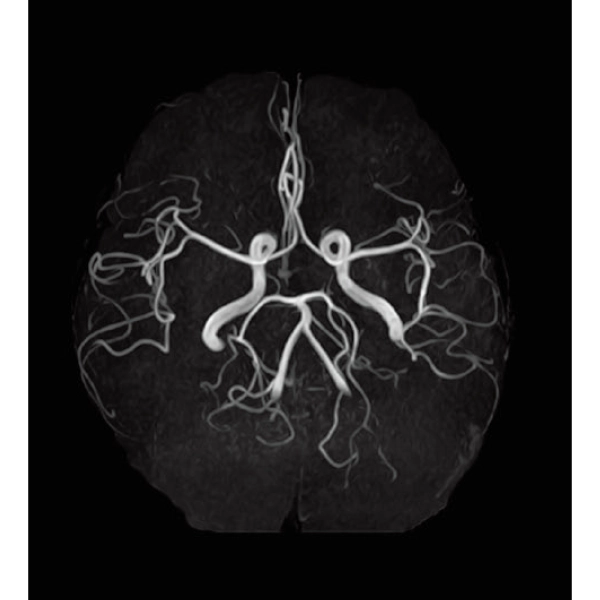

3DTOF MRA (MIP), 1:26

3DTOF MRA RADAR (MIP)